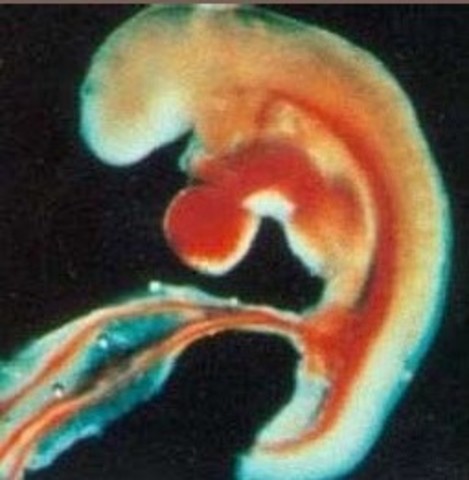

El corazón es un grupo de células musculares aletargadas y diminutas, pero que sobre los 22 días explota de vida. Una célula se contrae espontáneamente, contagiando a las contiguas y comienza una reacción en cadena hasta que todas las células del corazón empiezan a latir. Estas células están programadas para controlar los latidos del bebé hasta que el cerebro se haga cargo en las próximas semanas.